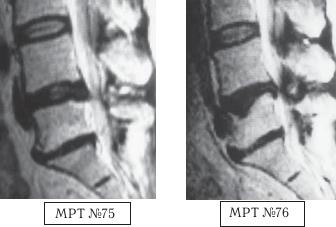

На МРТ № 71 наблюдается сглаженность физиологического лордоза, грыжа межпозвонкового диска в сегменте LV—SI, спондилёз на том же уровне, множественные грыжи Шморля, стеноз. На МРТ № 72 наблюдается помимо всего выше перечисленного ещё и компрессионный перелом тела позвонка LII и секвестрированная грыжа межпозвонкового диска в сегменте LV—SI, абсолютный стеноз спинномозгового канала. ![]() На МРТ № 73 — увеличенный фрагмент МРТ № 71 на уровне сегмента LI—LII, на котором наблюдается травма замыкательной пластинки LII позвонка, как следствие первых двух сеансов у этого «специалиста». На МРТ № 74 наблюдается увеличенный фрагмент МРТ № 72 на уровне сегмента LI—LII, на котором наглядно видны последствия третьего сеанса «вправления диска», и как следствие — компрессионный «пролом» тела позвонка LII и его замыкательной (гиалиновой) пластинки и внутренний разрыв межпозвонкового диска. Причина этой трагедии в элементарной безграмотности, причём не только того «аборигена-специалиста» образца XIX века, а и самого пациента. Ведь порой даже элементарные знания или хотя бы наличие здравого смысла одной из сторон способны уберечь человека от совершения роковой ошибки, повлекшей за собой тяжёлые последствия. Вот ещё один аналогичный случай с той лишь разницей, что такого же уровня «специалист», проводивший схожие манипуляции с пациенткой, именовал себя не «костоправом», а «мануальным терапевтом». Но здесь как в математике: «от перемены мест слагаемых значение суммы не меняется». ![]() На МРТ № 75 наблюдается состояние поясничного отдела позвоночника после нескольких месяцев лечения методом вытяжения: сглаженность физиологического лордоза, стеноз спинномозгового канала, грыжа межпозвонкового диска в сегменте LIV-LV, эпидурит на данном уровне, снижение высоты межпозвонкового диска в сегменте LV-SI вследствие развития в нём дегенеративно-дистрофического процесса, жировая дегенерация в телах смежных позвонков данного сегмента, спондилёз на данном уровне. На МРТ № 76 наблюдается состояние поясничного отдела позвоночника той же пациентки после нескольких сеансов лечения у мануального терапевта: кифотизация физиологического лордоза, абсолютный стеноз спинномозгового канала, грыжа межпозвонкового диска в сегменте LIV-LV, эпидурит на данном уровне, снижение высоты межпозвонкового диска в сегменте LV—SI, компрессионный перелом тела позвонка LV, усугубление дегенеративных процессов в сегменте LV—SI. Следующий пример наглядно показывает, как уже два разных мануальных терапевта участвовали в лечении пациента и, соответственно, какие результаты показали МРТ-обследования. Весной 2001 года данный пациент почувствовал боли, скованность в поясничном отделе позвоночника. Друг посоветовал «хорошего мануальщика». После первого курса (12 сеансов) пациент, по его выражению, «просто летал», однако через два месяца «крылья подрезало». Прошёл ещё курс мануальной терапии, стало легче, но боли полностью не прошли. Осенью того же года повторил курс лечения, боли только усилились, однако лечение продолжил. |